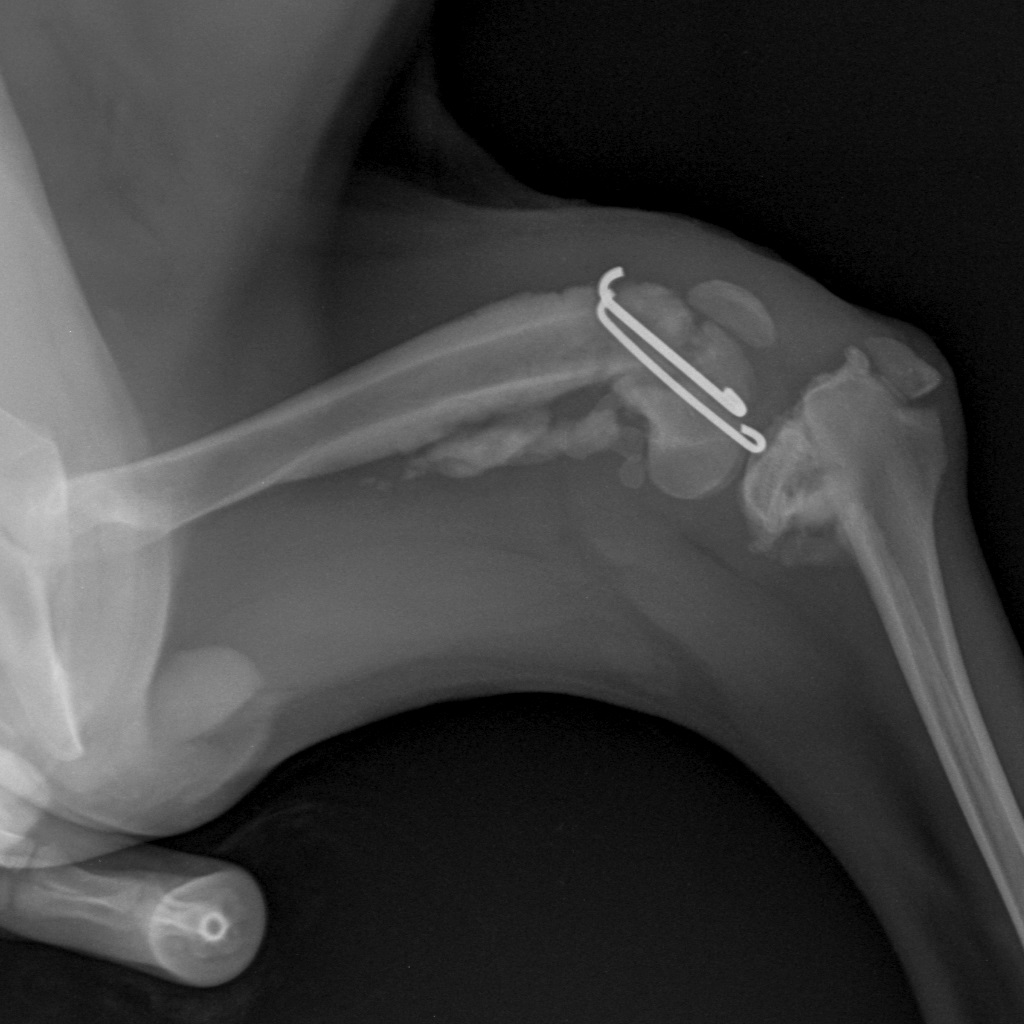

Скелет Мелкий  _ 10 kg-Колено LAT-04.11.2016-14_48_53-363 - копия.jpg

Вот такая бяка у девочки((

Такой мерзкий перелом бывает при прямом ударе по колену

Перелом ужасающий...

Жуть какой перелом! Далекому от медицины человеку - и то смотреть страшно. Впрочем, неудивительно если её из машины на ходу выкинули.